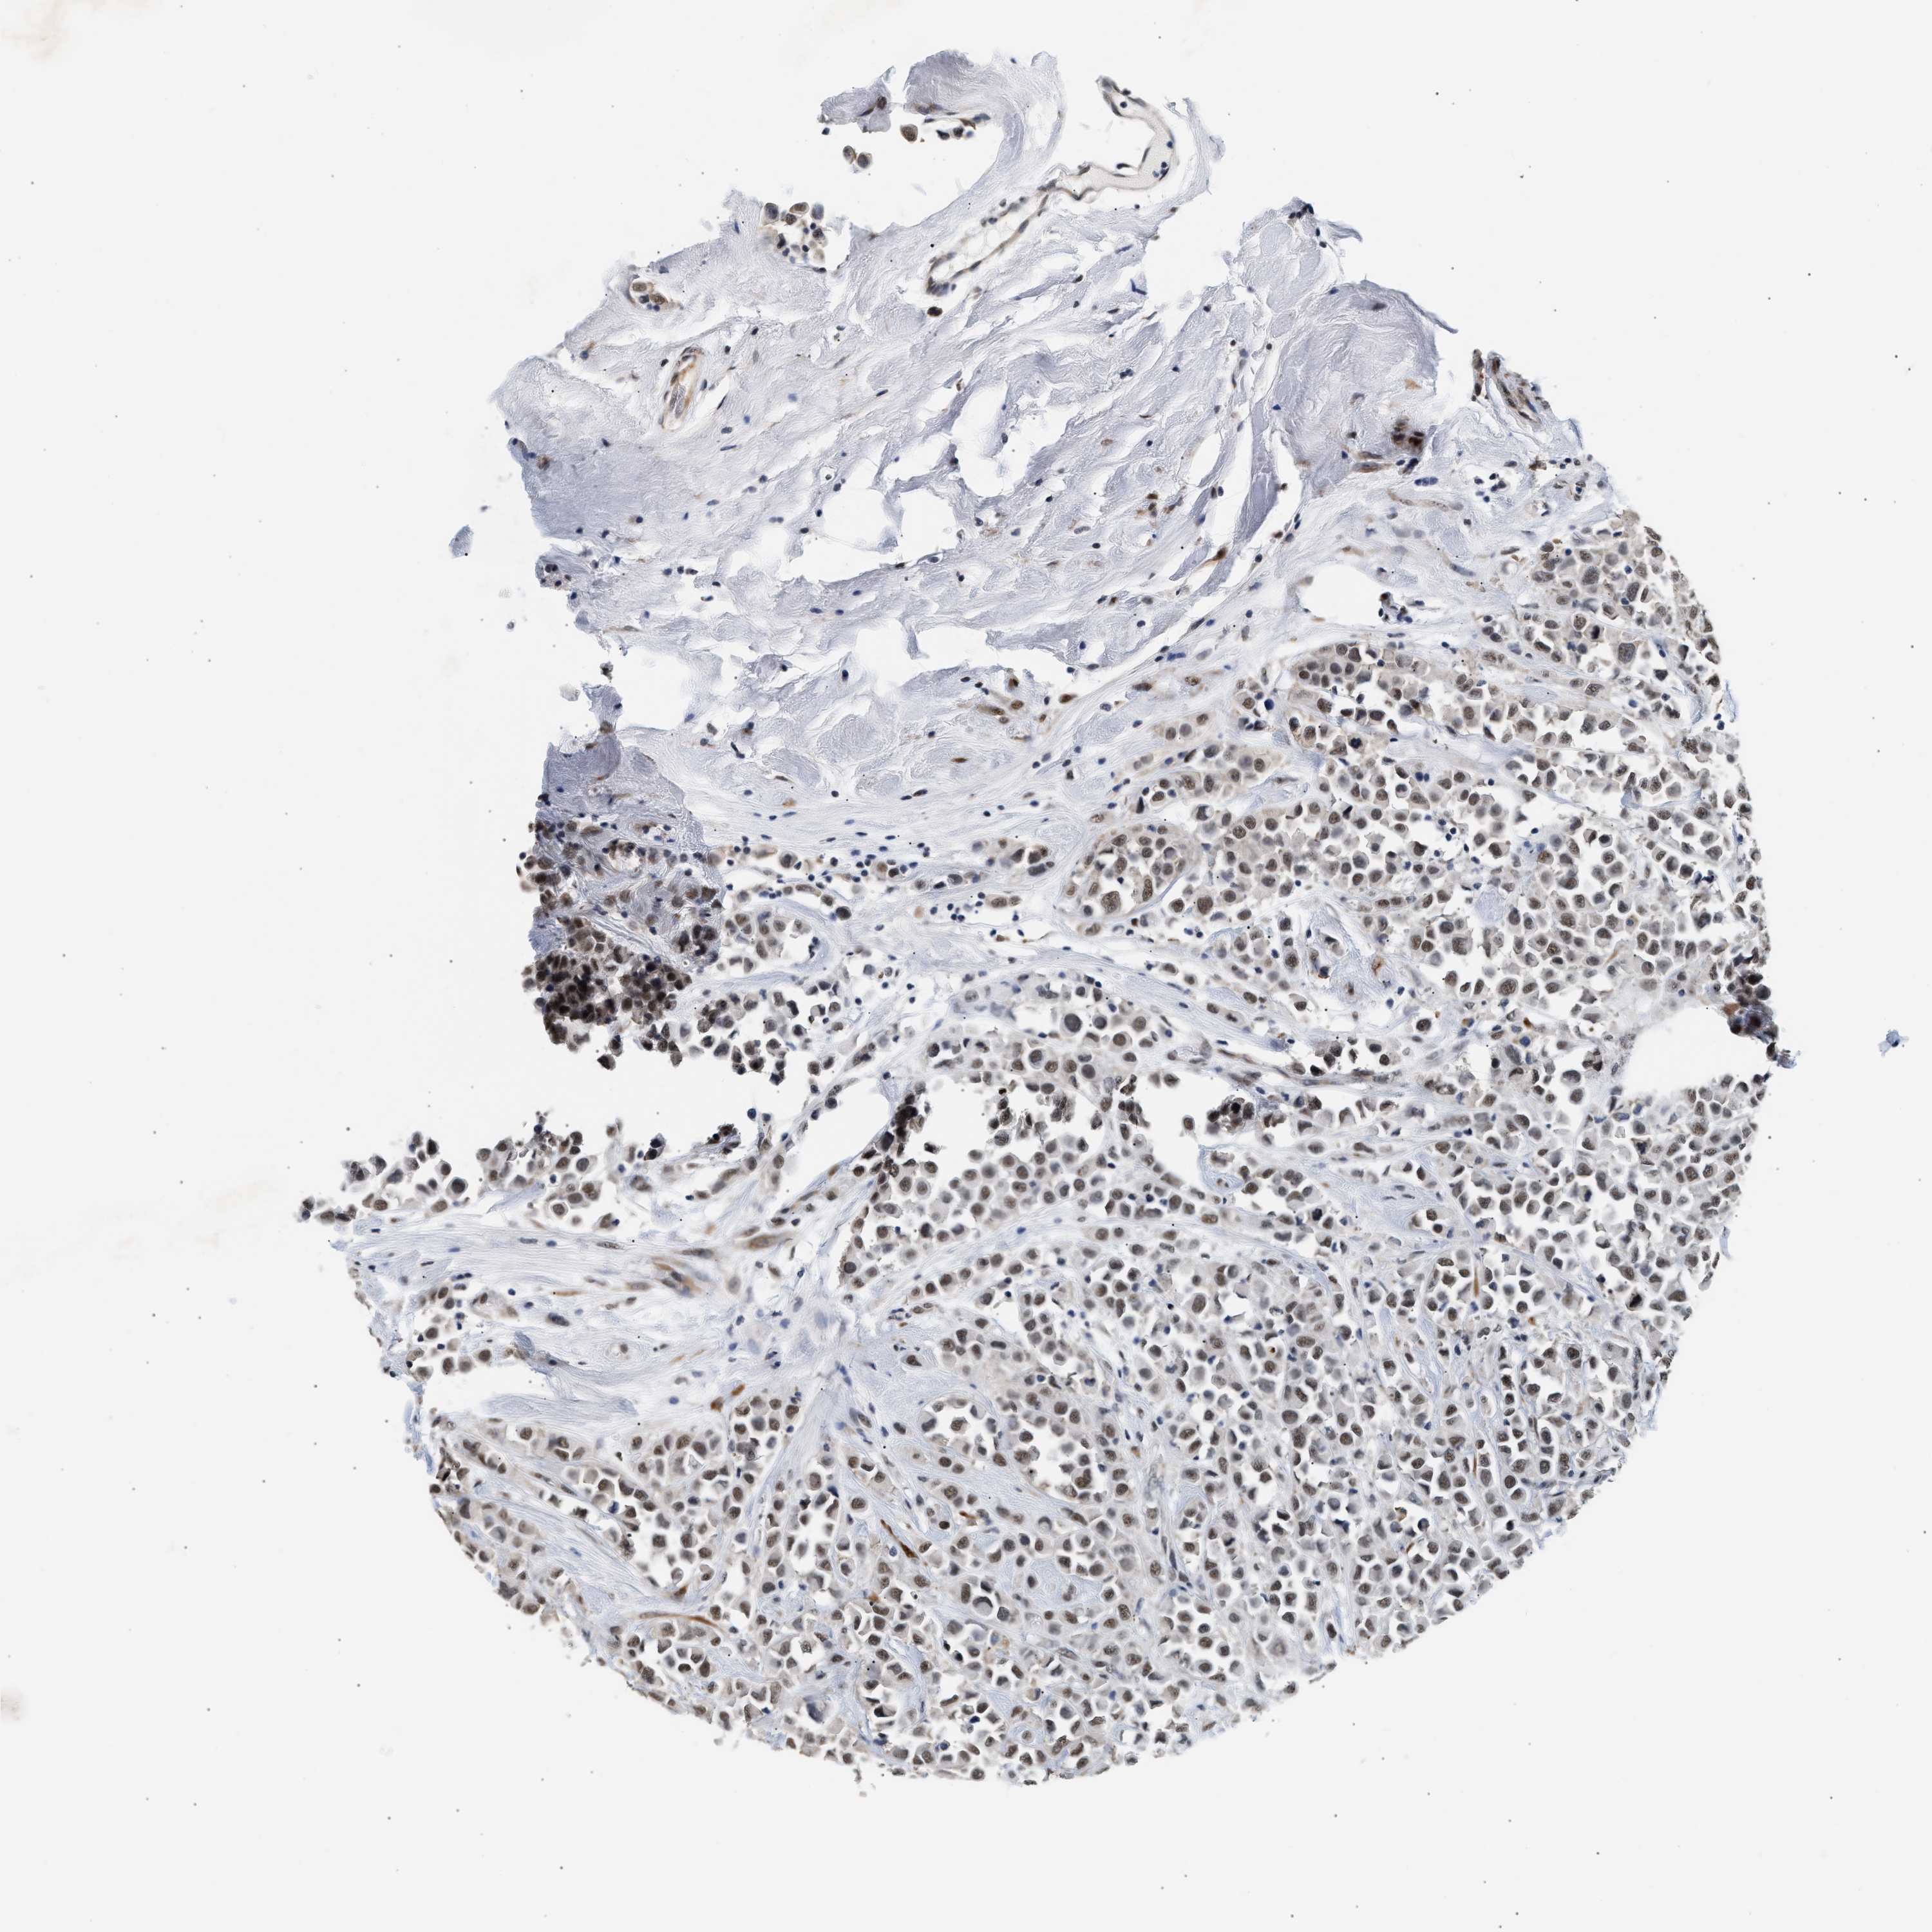

CANCER BREAST CANCER Show tissue menu

BRCA TCGA BRCA VALIDATION PROTEIN EXPRESSION